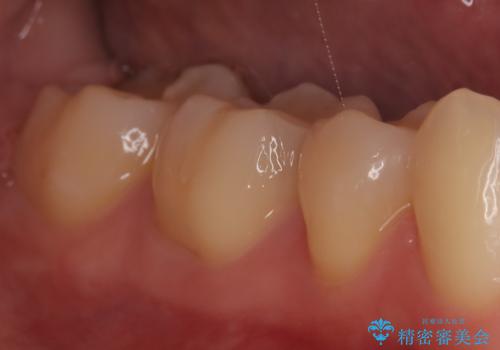

- 「銀歯を白しくしたい」を主訴に来院された患者さんです。

銀歯を外し、虫歯を除去した後にハイブリッドインレーで治療を行いました。

ハイブリッドインレーはセラミックと合成樹脂が混ざったものです。従って経年劣化や色の変化はあるものの、保険適応の被せ物に比べ、セラミックの含有率が高く、型取りの材料もシリコン材料を使用出来るので適合も優れています。